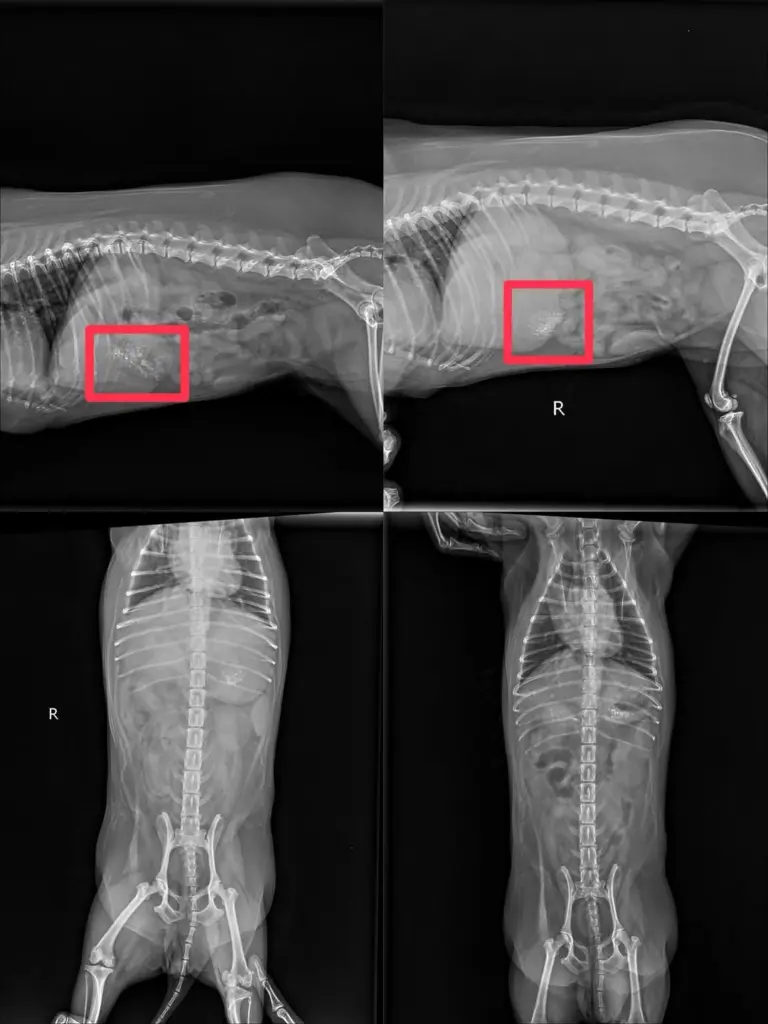

โดยโบกี้เผยว่าในตอนแรกเข้าใจว่าน้องหมีอาจมีปัญหาระบบทางเดินอาหาร เนื่องจากอายุมากแล้ว แต่เมื่อพาไปพบสัตวแพทย์และตรวจอย่างละเอียด ทั้ง X-ray, ส่องกล้อง และอัลตราซาวด์ กลับพบว่าในกระเพาะของน้องมี เศษสิ่งแปลกปลอมลักษณะแข็งคล้ายกระดูก ปูน และไม้ กระจายอยู่เต็มกระเพาะอาหาร

แต่หลังจากทานอาหารเปียกยี่ห้อหนึ่ง ก็มีอาการอาเจียนหนักมากกว่า 10 ครั้ง”🔸 “คุณหมอทำการล้างท้องแล้ว แต่ยังมีเศษสิ่งแปลกปลอมหลงเหลือในท้อง